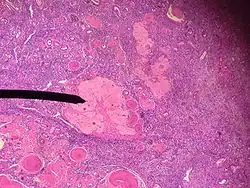

Human corpus albicans

The corpus albicans (Latin for "whitening body"; also known as atretic corpus luteum, corpus candicans, or simply as albicans) is the regressed form of the corpus luteum. As the corpus luteum is being broken down by macrophages, fibroblasts lay down type I collagen, forming the corpus albicans. This process is called "luteolysis". The remains of the corpus albicans may persist as a scar on the surface of the ovary.

The corpus luteum normally grows to about 1.5 centimeters in diameter, reaching this stage of development 7 to 8 days after ovulation. Then it begins to involute and eventually loses its secretory function and its yellowish, lipid characteristic about 12 days after ovulation, becoming the corpus albicans.[1] In the ensuing weeks, this is replaced by connective tissue and over months is reabsorbed.[2]